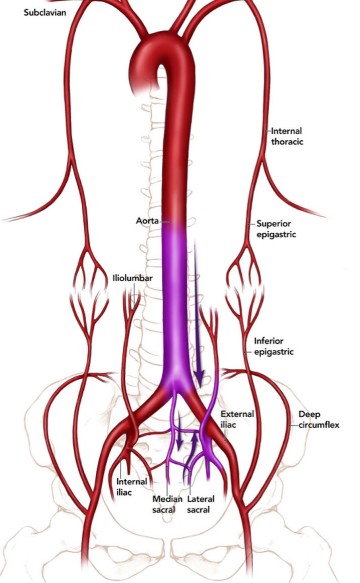

Collatérale de Winslow

- Voie de dérivation lors d’occlusion de l’artère iliaque externe

- Entre l’artère épigastrique supérieure et inférieure

- Subclavière → Mammaire interne → Epg-Sup → Epg-Inf → Iliaque Ext

Collatérale Paralombaires → Artère Circonflexe Iliaque Profonde / Iliaque Interne

Collatérales Sacrée Médiane → Iliaque interne